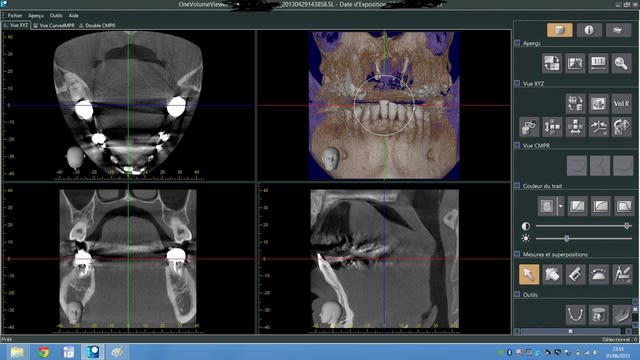

Voila comment cela se présente par défaut lorsque je mets la clé USB fournie pour le centre de radio.

Je pourrais ensuite modifier l'orientation de l'image 3D en haut à droite mais je pensais que par défaut c'était la bonne orientation : C'est donc faux ?

Pour te donner un exemple , sur simplant par exemple, tu dois tracer la courbe passant par le bord vestibulaire des dents , les coupes sont alors perpendiculaires a cette courbe.. Et donc perpendiculaires a la branche mandibulaire.